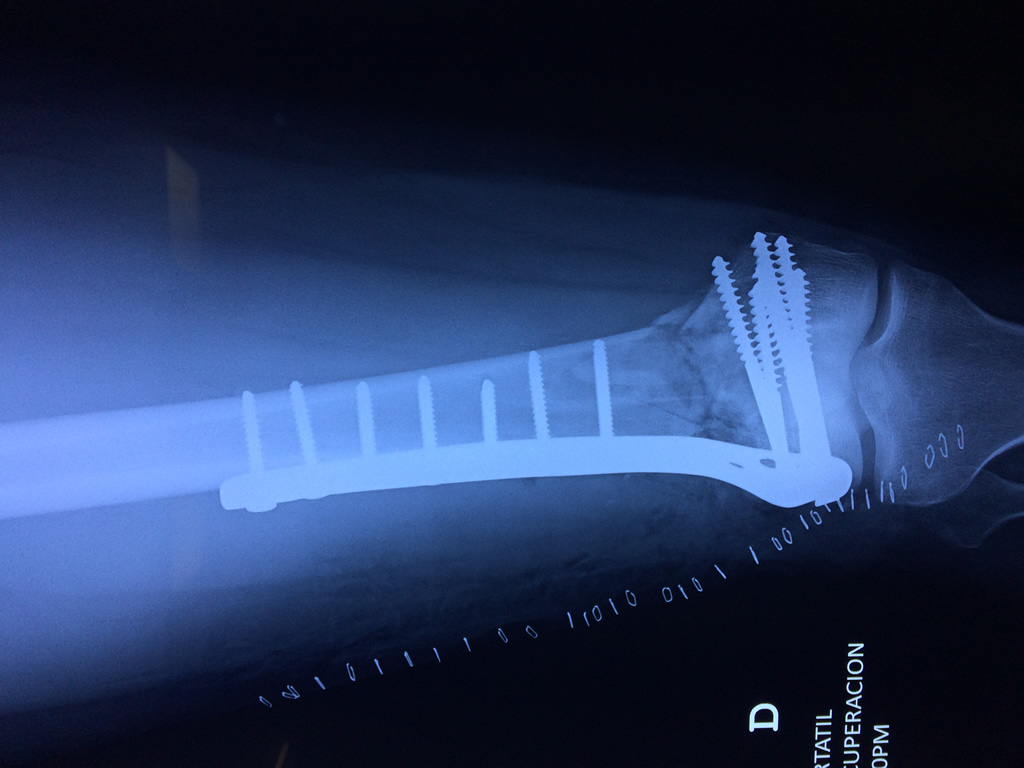

Calcaneo - Fémur

El fémur es el hueso del muslo, el segundo segmento del miembro inferior. Es el hueso más largo, fuerte y voluminoso del cuerpo humano.